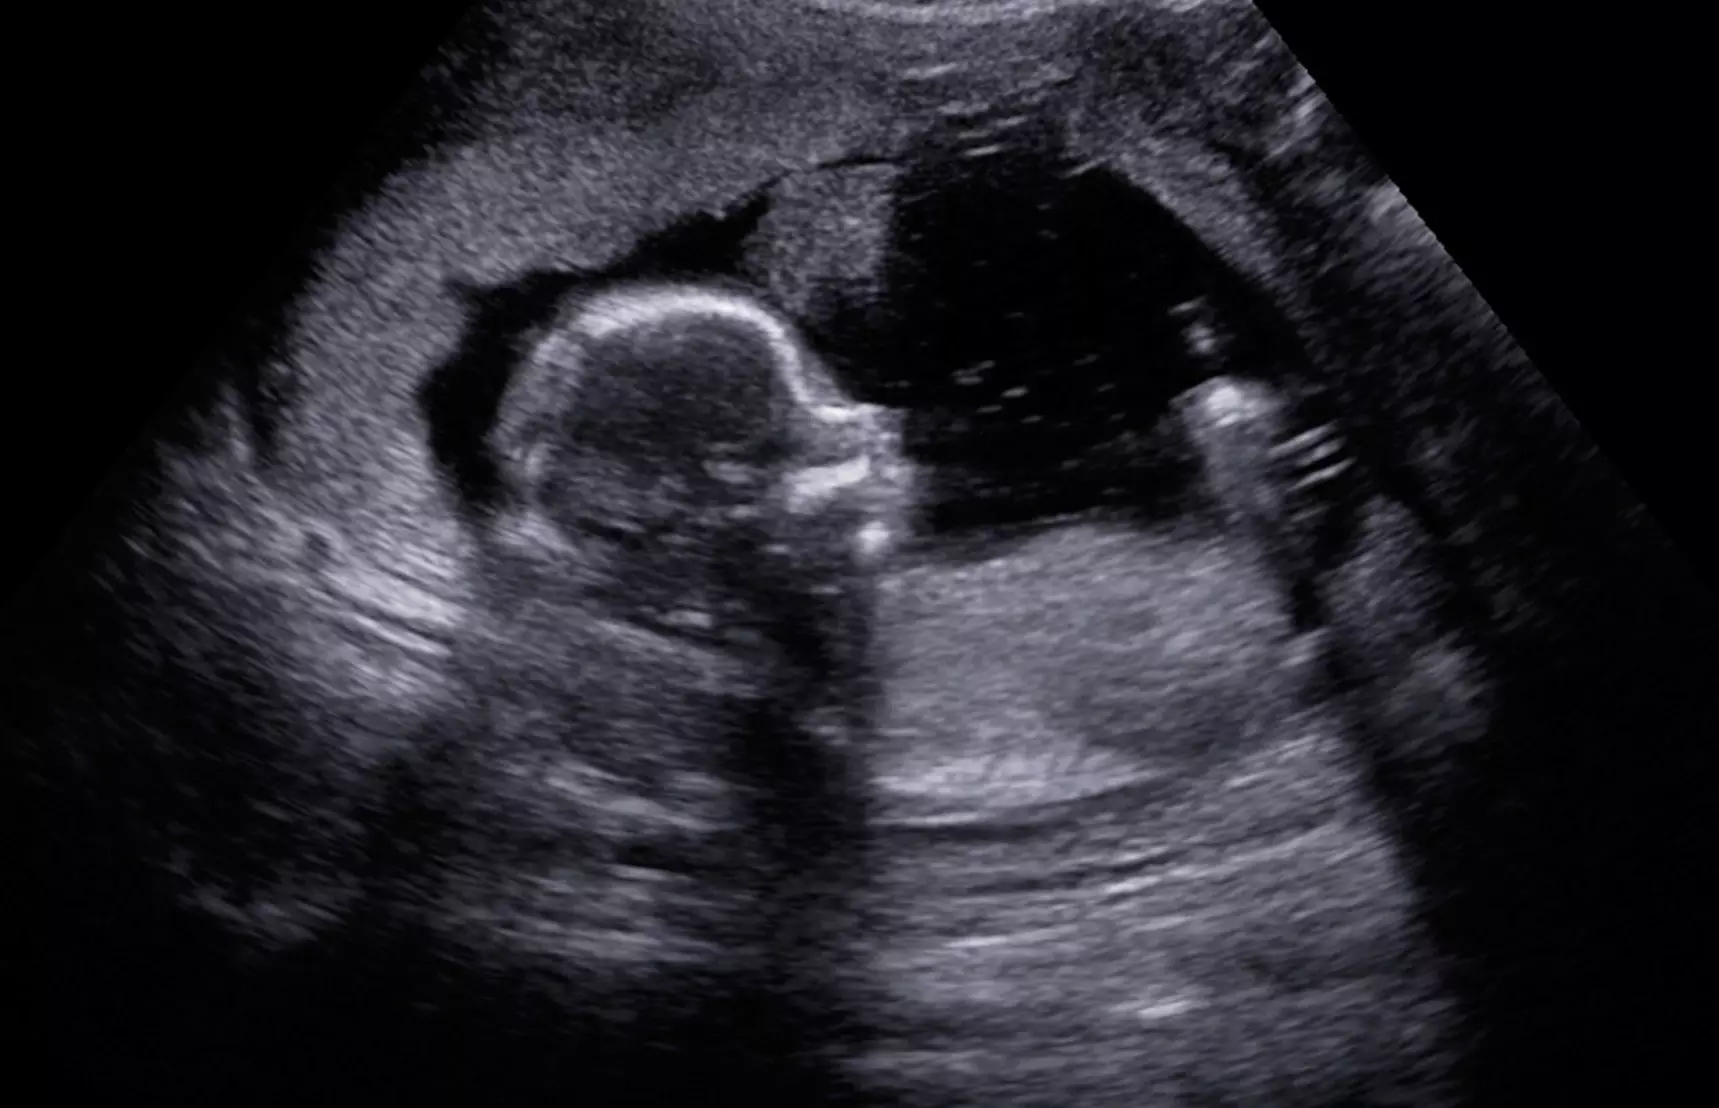

“The science has been clear for many years,” Boles said. “In the human embryo, the heart begins to beat and pump blood by 5 ½ weeks of gestation, or 3 ½ weeks after conception.”

Boles explained how at this point of gestation the myocardial tissue is tubular and does not yet have four discreet chambers, but it is doing what the adult heart does - pumps blood - and it is the first organ in the embryo to begin performing its intended function. This explanation is supported by a 2005 study published in the National Library of Medicine.

“Abortion’s science deniers would have us all believe that there is only random uncoordinated electrical activity at this point,” said Boles. “The science shows that not only is the activity coordinated at this point, it generates an EKG similar to that seen in an adult heart.”

“An ultrasound transmits sound waves into the body being studied and then measures the reflections from tissues and fluids of differing densities,” said Boles, “and also uses Doppler sound waves to detect fluid in motion. This is very similar to Doppler radar being used to detect the motion of the air and evaluate the weather.”

“The ultrasound does not detect the electrical activity,” he explained. “It detects the end result of that electrical activity, the rhythmic contractions of cardiac muscle tissue that result in the pumping of blood.”

A scientific article published by researchers at Oxford University in England also covered evidence that the human heart is beating by 5 ½ weeks.